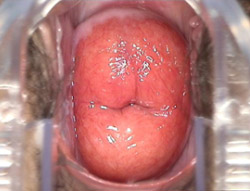

轻度宫颈糜烂的治疗方法哪种好?轻度宫颈糜烂,又叫宫颈糜烂一度,或者叫宫颈糜烂1度,是指宫颈的糜烂面积占到整个宫颈表面的1/3以内。天津武清妇科医院的专家介绍,患轻度宫颈糜烂时,患者一般无明显自觉症状,也可能仅有白带略微增多,但是常容易被患者忽略。许多患者的宫颈糜烂是在普查时或因其他妇科病就诊时被发现的。

轻度宫颈糜烂的治疗方法哪种好?天津武清龙济妇产医院专家介绍,“欧米修”超声聚焦技术是近年发展起来的专门用来微创性诊断和治疗宫颈炎症的前沿技术,是现代工程技术和医学相结合的产物。作为一种非侵入性治疗方法,“欧米修”超声聚焦技术可将超高频电磁波强大的能量聚焦于病变处,并导致蛋白变性及病变组织细胞不可逆性坏死,促进组织重建,改善微循环,从而达到消除炎症、修复宫颈、不损伤正常组织的目的。